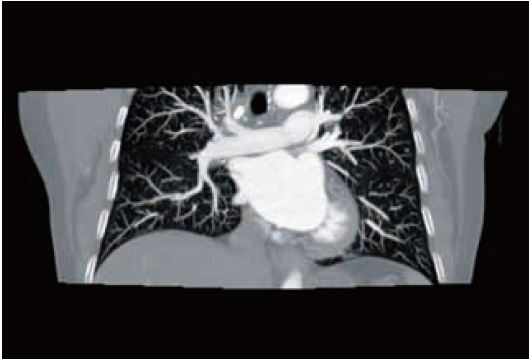

Рис. 5 КТ-ангіографія з вільним диханням та одним обертом – 80 кВ. 30 мл ніопаму 370 при 3 мл/с. Доза 0,5 мЗв. Велика емболія легеневої артерії закупорює праву легеневу артерію (стрілка).

Pис. 6 ТЕЛА та розшарування аорти можна виключити в одній ротації як правило, при <1 мЗв. 30 мл ніопаму 370 при 3 мл/с.